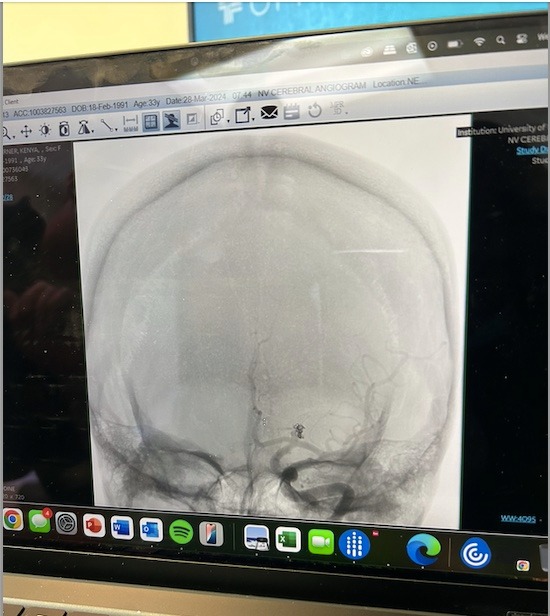

My name is Kenya, and I am raising funds for my medical recovery for a critical, life-saving surgery. I was diagnosed with a ruptured brain aneurysm as a teenager, which continues to affect me today. I have struggled with medical trauma that delayed further treatment, but thanks to therapy (yay, therapy! lol), I’ve overcome my fears and I'm now ready to undergo the much needed procedure to clip my aneurysm.